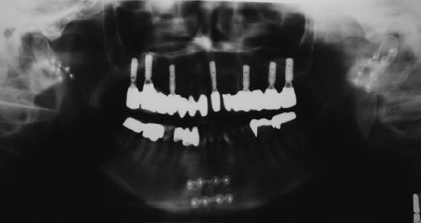

CHAPTER The long-term outcome after jaw fractures depends not only on the type of fracture and the precise restoration of the broken bone, but also on the integrity of all anatomic structures neighboring the fracture. Choosing the appropriate surgical approach is an additional key factor for avoiding complications. This chapter focuses on the management of upper and lower jaw fractures. Direct and indirect forces to the lower and upper jaw result in fractures. Several low-resistant anatomic locations with thinned bone are prone to fractures. Typical fractures (Fig. 47.1) of the maxilla include the so-called Le Fort I fracture, in which the maxilla breaks off the midface (A in Fig. 47.1), and sagittal fractures (see B in Fig. 47.1), which involve transverse expansion of the upper jaw. With regard to the mandibular bone, the parasymphyseal (see C in Fig. 47.1) and the angle (see D in Fig. 47.1) regions are prone to fractures. The extended root of the lower canine and the foramen of the mental nerve are responsible for parasymphyseal fractures, whereas retained wisdom teeth are a determinant in angle fractures. The thin condylar neck (see E in Fig. 47.1) including the condylar head (see F in Fig. 47.1) is another fragile region of the mandible. High-velocity trauma leads to comminuted fractures (see G in Fig. 47.1). In particular, the uncompleted median symphysis in children is highly vulnerable. Pathologic conditions of the bone such as osteomyelitis or osteonecrosis (see H in Fig. 47.1) increase the risk of fractures, as does an edentulous, highly atrophied body of the mandible1,2 (see I in Fig. 47.1). The anatomical complex of the upper and lower jaw is functionally involved in clenching and speaking, but also plays a significant role for facial aesthetics. Restoration of painless unlimited mouth opening, laterotrusion, and protrusion is one of the main targets after jaw fracture. Perfect occlusion should be recovered in dentate patients, and the harmonic red-white aesthetics of teeth and gingiva should be reestablished. As a basis for later prosthetic rehabilitation, the accurate positioning of the maxilla and mandible in the vertical, transversal, and sagittal dimension is always necessary.3 Undesirable results after treatment of jaw fractures arise, in most cases, because of deficient clinical and radiological diagnostics and insufficient treatment planning.4 To a lesser extent, poor outcome results from the failure of the patient to cooperate or from a lack of postoperative care. Open reduction and internal fixation (ORIF) is the basic reconstructive principle in nearly all types of jaw fractures. Since their development in the 1970s, titanium miniplates represent the osteosynthesis material of first choice for the maxilla and for the mandible.5 Fundamental publications have described the buttresses of the facial bones.6 Most postoperative complications can be avoided when the rules of miniplating along the natural strains of the bones are strictly observed. For exceptional cases in which bone has been sheared off, lag screws might be a therapeutic alternative. Particular attention must be paid to jaw fractures in childhood. The jaw bones of children have a high potential for bone remodeling. Reconstructive principles have to be modified; closed reduction is a sufficient therapy in many cases.7 If ORIF is conducted, plate removal must be performed much earlier. Fig. 47.1 Types of jaw fractures (blue, maxillary fractures; red, mandibular fractures). A, Le Fort I fracture. B, Sagittal upper jaw fracture. C, Parasymphyseal fracture. D, Angle fracture. E, Fracture of the condylar process. F, Fracture of the condylar head. G, Comminuted fracture. H , Pathologic fracture (osteomyelitis, osteoradionecrosis, medication-related osteonecrosis). I, Fracture of the atrophic jaw. This chapter concentrates on the most challenging types of jaw fractures, because of their high potential of therapeutic failure. After the breaking off of the midface, the pterygoid muscles pull the fractured upper jaw into a dorsal position. Nonocclusion, open bite, and nasal airway restriction result. In the long term, the facial profile changes by the retral position of the maxilla and the subnasal region. The patient presents with pseudoprogernia. When reducing the fracture, retral positioning of the maxilla must be avoided, and particular attention should be paid to the exact positioning of the maxilla. A posteriorly impacted maxilla must be pulled forward. Significantly delayed cases should be reduced with Rowe’s maxillary disimpaction forceps. The two-pronged instrument grasps the maxilla with a palatal blade and a blade positioned in the nasal cavity. After reduction, meticulous mandibulomaxillary fixation is necessary to secure the occlusal relationship until osteosynthesis with miniplates is performed. After ossification of the malpositioned maxilla, a secondary correction must be carried out. Preoperative planning is therefore indispensable. First, plaster models from the maxilla and mandible are made, a checkbite is performed, and the positions of the maxilla with respect to the temporomandibular joint (TMJ) and the cranial base are determined with a face-bow. To imitate the position of the jaws and the mandibular movements, upper- and lower-jaw casts are positioned correctly in an adjustable articulator. With respect to the posttraumatic and intended facial profile, occlusion and aesthetics model osteotomy is performed on the casts. The exact movement of the maxilla in three dimensions is ascertained and marked on the model. Occlusal splints, namely a starting splint and a postosteotomy splint, are made on the basis of the model operation. These splints are fixed between the maxilla and the mandible during the Le Fort I osteotomy. Summary Box Unfavorable Results and Complications Associated with Fractured Jaw Repair Maxilla Fractures • Le Fort I fractures – Open bite – Nasal airway restriction • Sagittal fractures Mandibular Fractures • Plate exposure • Injury to mental nerve • Injury to root of lower canine • Infection Condylar Process Fractures • Malocclusion • Condylar absorption • Arterial hemorrhage • Nonocclusion • Reduced mouth opening • Limited mandibular movement • Osteonecrosis • Scarring • Facial nerve paralysis • Parotid fistulae • Infection • Scarring stenosis of the auditory canal • Dislocation of osteosynthesis material Comminuted Fractures • Discontinuity of the bone • Infection (abscesses, cellulitis, osteomyelitis) • Nonunion and malocclusion • Nerve injury Pathologic Fractures • Class A • Class B • Class C Atrophic Jaw Fractures • Complication in bone healing • Stability loss of mandible • Extraoral plate exposure • Intraoral plate exposure • Fractured osteosynthesis material Childhood Jaw Fractures • Facial asymmetry • Malocclusion/open bite • Joint ankylosis Secondary correction of maxilla malpositioning can also be carried out by virtual planning of a Le Fort I osteotomy. Once a computed tomography (CT) scan of the middle and lower face is obtained, the data is prepared with a special software to gain a virtual three-dimensional model. The required movement of the maxilla can be simulated, and individual cutting guides and osteosynthesis material for the Le Fort I osteotomy can be produced by industrial partners within a few days.8 Sagittal fractures are accompanied by transverse malposition, resulting in transverse expansion of the maxilla and nonocclusion. In some cases, sagittal fractures with extensive dislocation cause lacerations of the palatal soft tissues with oronasal communication. The alveolar process is often tilted, which makes it difficult to achieve a sufficient occlusion solely by maxillomandibular wiring. The fabrication of an individual acrylic palatal plate might be indicated for better stabilization of the palatal vault. After this pretreatment, osteosynthesis is carried out with miniplates being placed on the frontal part of the maxilla. Additional problems might arise from laceration of the palatal gingiva. Primary tension-free closure is challenging, because mobilization of the palatal soft tissue is nearly impossible. As an unfavorable result, a persistent oronasal fistula might occur. Closure of such fistulas is hampered by scarring. The use of a pedicled palatine flap and the mobilization of the buccal fat pad are therapies of the first choice for oronasal fistula closure. Techniques for the closure of recurrent or extended oronasal fistulas are associated with much more donor site morbidity and include the tongue flap or a radial forearm flap (Fig. 47.2). Fig. 47.2 Persistent oronasal fistula after sagittal fracture of the maxilla. (a) After repeated trials of primary closure. (b) Final closure with a tongue flap. The treatment of these types of mandibular fractures is based on the miniplating techniques developed by the group led by Champy9 in the 1970s. With the exception of the angle region, two monocortical fixed miniplates (four-hole or six-hole) are placed on the buccal surface of the mandible. Whereas one plate is fixed below the dental roots, the other one is fixed at the mandibular base to neutralize moments of torsion (Fig. 47.3). In the angle region, the muscle sling of the masseter and medial pterygoid muscles compresses the strains of the mandibular base. Therefore placement of a single plate running from the postmolar oblique line to the buccal molar region is adequate. If the principles of miniplate osteosynthesis are fulfilled, complications are rare. Unfavorable results such as plate exposure can arise when the intraoral incision is placed directly over the fixed titanium plates. Postoperative smoking and poor oral hygiene are cofactors that increase the risk of plate exposure. Particular attention must be paid to the mental nerve and the root of the lower canine in parasymphyseal fractures. Injuries of these anatomic structures from incorrect placement of screws and miniplates can easily be avoided. If plate exposure occurs, further infection of the region must be prevented. Strict oral hygiene must be maintained, including antiseptic mouthwashes, and the patient must be seen weekly in the maxillofacial outpatient clinic. Osteosynthesis material removal is delayed to at least 2 months to allow bony consolidation to be completed. The treatment of condylar fractures is a controversial topic. During the past decade, much effort has been made to improve the outcome of condylar fractures, but after critical consideration, many of the “new techniques” have been abandoned as fast as they have emerged. Taking all conflicting points into consideration, the surgeon has the choice of treating all cases conservatively or performing ORIF on the other. Various complications arise after the fracture and treatment of the condylar neck and head. Functional, aesthetic, and neurosensory deficits are common.10 Malocclusion, reduced mouth opening, and limited mandibular movement are often associated with the pterygoid lateral muscle pulling at the fractured and nonfractured fragments.1 Malocclusion also results because of the dislocation of the condylar process and subsequent reduction of ramus height. Osteonecrosis of the condyle might be an unfavorable result of traumatic or iatrogenic disruption of the blood supply to the small broken fragment. Surgery-associated problems include unfavorable scarring and facial nerve paralysis, mostly of the marginal mandibular branch, after use of an extraoral approach for ORIF. In addition, parotid fistulas and sequential infections have been described after a transcutaneous transparotid approach to the fractured condylar process. Scarring and subsequent stenosis of the auditory canal is also a problem that arises after ORIF of condylar head fractures through a retroauricular approach.10 Fig 47.3 Management of mandibular fractures. (a,b) Radiologic diagnostics are performed in two planes with panoramic and mandible posteroanterior radiographs. (c) Maxillomandibular fixation with screws and wires. (d) Open reduction and internal fixation with miniplates considering the anatomy. The technique of the anatomic repositioning of the condylar head fragments with trapezoid plates and successive definitive screw fixation to the stable mandible can result in the dislocation of osteosynthesis material. A via falsa of the inserted screw with significant harm to surrounding structures can occur. Although bleeding from the external auditory meatus is common after posterior dislocation of the condylar head, the penetration of the fractured condyle to the middle cranial fossa might, in rare cases, result in life-threatening infections and complications.11 Modern diagnostics of condylar process fractures should not rely only on clinical parameters and plain radiographs such as panoramic and mandible posteroanterior radiography. Mandible posteroanterior radiographs might provide a hint to the grade of dislocation of the fractured segment. For an exact classification of the segment and determination of the treatment concept, a further investigation with a three-dimensional technique (computed tomography [CT], cone beam computed tomography [CBCT]) is required. Exact and reliable control of the post-therapeutic effect on the posttraumatic state can only be achieved by CT and CBCT. The condylar fracture classifications of Spiessl et al.12 and Loukota et al.13 are helpful in determining whether the fracture should be done operatively and which surgical approach is the most suitable. The classification by Spiessl et al.12 (Fig. 47.4) suggests that ORIF is definitely indicated for healthy adults with type IV and type V fractures (Box 47.1). Luxation of the condylar head out of the TMJ socket is associated with a massive loss of vertical height and nonocclusion and, in bilateral luxations, with the development of an iatrogenic malpositioning of an adjusting screw and retral position of the mandible. Therefore the repositioning of the condylar process and the securing of this position by osteosynthesis is essential (Fig. 47.5a). The classification by Spiessl et al.12 does not differentiate between the severity of dislocation in type II and type III fractures. Dislocated fractures with a deviation of the condylar process of less than 30 degrees can be treated by maxillomandibular fixation and early functional therapy (Fig. 47.5b). This suggestion includes, in particular, unilateral cases, cases without loss of vertical height, and posttraumatic normo-occlusion. Wired arch bars for maxillomandibular fixation should be used in all cases with slight dislocation. In type I and type VI fractures without dislocation, I recommend four bone screws be placed between the roots of the canines and the first premolar carefully avoiding violation of the teeth or their roots. During the first postoperative week, maxillomandibular fixation must be ensured by rigid elastics (type III and IV), after which soft elastics (type VI to VIII) are indicated for another 3 weeks. Soft elastics should allow mouth opening and alleviate functional therapy. Rigid maxillomandibular fixation should be limited to 2 weeks, especially in younger patients, to prevent bony ankylosis of the TMJ. Radiographic observations after maxillomandibular fixation are essential to detect spontaneous dislocation during manipulation at an early stage. If this occurs, secondary ORIF is necessary. Fig. 47.4 Fracture types of the mandibular condyle as classified by Spiessl et al, with indications for open reduction and internal fixation marked in pink. Open reduction and internal fixation (ORIF) is recommended in mandibular condyle fractures with the following characteristics: • Luxated condylar fragment • Dislocation of the condyle of more than 30 degrees • Massive loss of vertical height Exceptions to the algorithm can/must be: • Posttraumatic normo-occlusion • Multimorbid patients with potential life-threatening risk during narcosis • Children younger than 12 years with a high potential of condylar remodeling • ORIF is indicated (even in slight dislocations) in*: Fig. 47.5 Indications for open reduction and internal fixation in fractures of the mandibular condyle. (a) Loss of vertical ramus height. (b) Dislocation of the condylar fragment of more than 30 degrees. Because of the earlier mentioned risks of ORIF in condylar head fractures (condylar head resorption, stenosis of the auditory canal, facial paralysis, and dislocation of osteosynthesis material), I recommend closed reduction with functional therapy in such cases. If primary therapy results in nonocclusion, I recommend orthodontic therapy followed by secondary orthognathic surgery after several months. Loss of vertical height can be corrected by vertical ramus osteotomy. Loukota et al.13 published a new classification of condylar fractures in 2005. They defined an anatomic A-line that crosses the most inferior point of the semilunar incisure of the mandible. The A-line starts as a perpendicular line to a tangent touching the most posterior points of the ramus and the condylar head13 (Fig. 47.6). To define the surgical approach, The A-line is an extremely helpful tool for determining the surgical approach (Fig 47.7). Although numerous approaches to the mandibular condyle have been developed, I rely on three main approaches depending on the anatomic position of the fracture with regard to the A-line. Condylar base fractures located inferior to the A-line are reduced via an intraoral approach (Fig. 47.7a), condylar base fractures running through the A-line are treated by a retromandibular approach (Fig. 47.7b), and condylar neck fractures superior to the A-line are reduced via a rhytidectomy-transparotid approach (Fig. 47.7c). The latter approach can be extended as a preauricular incision superior to the temporal region if the condylar head region must be reached (Fig. 47.7d). Fig. 47.6 Anatomic relationship in fractures of the condylar process. The A-line is a perpendicular line to the mandibular ramus tangent running through the inferior part of the incisure of the mandible. Fig. 47.7 Recommendation for the surgical approach with respect to the anatomic location of the condylar fracture. When approaching a condylar base fracture transorally, the overview to the backside of the ascending ramus is reduced. Nevertheless, correct repositioning of the fragments is essential, and hooks and retractors are helpful. However, iatrogenic injuries caused by pulling forces to the retromandibular vein and the accompanying marginal mandibular branch of the facial nerve must be avoided. In the early 2000s, the technique of endoscopic revision of condylar fractures via a transoral approach was commonly cited in the literature.14,15 However, four main complications are common with this technique: 1. Arterial hemorrhage 2. Facial nerve injury 3. Nonunion 4. Partial condylar reabsorption After critical analysis of their results, Arcuri et al.16 believe that this is not an ideal approach for a subcondylar fracture but might be an alternative procedure in selected cases. With the retromandibular approach (Fig. 47.8), the surgeon must pay particular attention not to injure the marginal mandibular branch of the facial nerve. Therefore it is useful to prepare the retromandibular vein after skin incision (see Fig. 47.8b) and to visualize the nerve (see Fig. 47.8c). The periosteum is cut anterior to the marginal mandibular branch, and the fracture is exposed (see Fig. 47.8d). The vestibular surface and the posterior rim of the ramus are prepared to obtain a complete overview of the fractured bone. Distraction of the anterior mandible is commonly necessary to reduce the dislocated fragments anatomically. The algorithm recommends a rhytidectomy anteroparotid-transparotid approach for condylar neck fractures. To prevent complications involving the facial nerve, a strictly subcutaneous preparation is necessary after skin incision. The capsula of the parotid gland is either saved when carrying out an anteroparotid approach or dissected horizontally when a transparotid approach is used. When the anteroparotid approach is used, dissection is carried out subcutaneously until the masseter muscle is reached in front of the gland and until the overlying nerve branches have become obvious. Attention must be paid to leaving the excretory duct of the gland intact. The parotid gland is then retracted backward, and the masseter muscle is cut horizontally between the two nerve branches. The fracture can be exposed and anatomically reduced. After osteosynthesis, meticulous control of hemorrhage is essential. Reconnection of the masseter muscle with 3–0 or 4–0 resorbable suture is also mandatory to restore its function. A suction drain is inserted before skin closure to prevent hematoma and hematoma-induced facial nerve palsy. Cutaneous closure is performed with 4–0 or 5–0 nonresorbable sutures to prevent scarring. The transparotid approach involves cutting the parotid capsule parallel to the nerve branches. Nerve branches must be detected by an electrostimulation device. The incision of the capsule is marked with sutures to visualize it later. After dissection of the gland and the masseter muscle, a more direct view of the fracture becomes visible than via the anteroparotid approach. However, the masseter muscle must be reattached and the capsule closed tightly after osteosynthesis. Tight capsular closure is essential to prevent salivary fistulas that might occur in about 1% of the cases.17 Treatment of salivary fistulas or sialoceles can be either carried out surgically by reevaluation of the parotid or conservatively. Acceptable conservative regimens include, as a first step, compression bandaging and drainage and, as a second step, the insertion of a feeding tube for 8 days and additional administration of antisialogogs.18 A single injection of botulinum toxin type A to the parotid gland has also been described as a promising therapy.19 Fig. 47.8 The retromandibular approach for a condylar base fracture. (a) Preoperative marking of the anatomic landmarks and incision. (b) Preparation of the retromandibular vein. (c) Exposure of the marginal mandibular branch of the facial nerve anterior to the retromandibular vein. (d) Visualization of the fracture. Fig. 47.9 Fatigue of osteosynthesis material and consecutive plate fractures in both condylar regions. Fig. 47.10 Correct angle of 30 degrees between two 2-mm miniplates in a condylar base fracture. (a) Intraoperative view after open reduction and internal fixation. (b) Postoperative control using cone beam computed tomography. Osteosynthesis is one of the most important, if not the key procedure in the surgical treatment of condylar fractures. Many osteosynthesis systems are available. Special osteosynthesis plates and screws have been developed to fulfill the requirements of the mandibular condyle (e.g., lag screws, triangular plates, locking plates, resorbable plates). The system must fit the usually small condylar fragments, be adaptable via the restricted approach, and withstand bite forces (Fig. 47.9). The correct placement of the osteosynthesis material into the condyle process and the mandible has been the matter of myriad investigations. Tensile and compression forces to the mandible and its condylar process have been measured by photoelastic analysis, three-dimensional biomechanical simulation models, and finite element models.20–22 The results of these investigations stress that two-plate fixation with 2-mm four-hole miniplates is superior to all other stabilization techniques.22,23 Meyer and colleagues24 states that “more and more authors advocate the use of two miniplates. The first is placed in the axis of the condylar neck as usual, and the second is placed obliquely under the mandibular notch.”24 In my own experience and in accordance with Meyer,24 two miniplates are needed. After anatomic reduction of the fracture, the first four-hole miniplate is placed in the axial direction of the condylar neck. With gracile condylar necks, particular attention should be paid to ensure that the first plate is placed posteriorly enough for the second to be positioned anteriorly. Monocortical screws of 5 mm or 6 mm are used to fix the plate. After this maneuver, a control of the occlusion is recommended. If the occlusion is correct, the second plate is placed (according to the natural strains) 30 degrees in an anterior direction to the first, and all screws are drilled in (Fig. 47.10). The gold standard for postoperative control is three-dimensional radiographic observation by CT or CBCT. Postoperative radiography is essential, not only for forensic reasons. Exact and detailed documentation of the pretreatment and post-treatment status can be of high value if complications—such as malocclusion; mastication pain; or nearthrosis, pseudarthrosis, or ankylosis—arise. Secondary dislocations of the nonoperated site might occur, especially in bilateral condylar fractures with unilateral conservative treatment. Distraction maneuvers during anatomical reduction can often cause these dislocations. In consequence, secondary corrections with ORIF have to be performed. Comminuted fractures occur after high-velocity trauma or shotgun injuries. They are characterized by bone that is crushed into a number of smaller fragments. For this reason, anatomic repositioning can be extremely difficult. Osteosynthesis is hampered by the lack of fixation options for the small bony segments. Because of the trauma mechanism, comminuted fractures are often associated with remarkable injuries to the neighboring tissues, with lacerations of the gingiva and facial skin or even the loss of soft tissue with subsequent defects. The prevalence of fractured, loosened, or knocked-out teeth in these types of injuries is high. Foreign bodies or bullets penetrate soft tissue and bone. In addition to the difficulties of anatomic repositioning and stabilization of the bony fragments, several complications can arise with this type of fracture: • Discontinuity of bone • Infection, mainly as abscesses, cellulitis, or osteomyelitis because of the following: • Nonunion or malocclusion • Nerve injuries The discontinuity of bone results primarily after traumatic loss of a bone fragment or secondarily because of infection and necrosis of a segment. In extended comminuted fractures, a step-by-step approach is recommended to prevent the previously mentioned complications and unfavorable outcomes. First, wounds are cleansed with polyhexanide 0.4% or Ringer’s lactate solution via a syringe; then the surgeon performs a meticulous search for foreign material and tooth fragments. Foreign material, dental fragments, and teeth with vertical fractures and pulp exposure are removed. Teeth in malposition are manually replaced into their sockets without touching the root region. These teeth are fixed with interdental titanium-composite splints for stabilization. If occlusion is reproducible, maxillomandibular fixation is performed, and intraoral soft tissue is closed if necessary. Thereafter the mandible is (if possible) stabilized in occlusion, and the fracture is manually reduced via an extraoral approach. The separate fragments are first allocated and fixed with miniplates and screws. Small fragments that are impractical to fix are removed to prevent dislocation, infection, and necrosis. Subsequently, a load-bearing reconstruction plate is placed on the mandibular base to maintain the mandibular block, particularly when there is a discontinuity of the bone (Fig. 47.11a–c). If bone segments are missing and no obvious signs of infection (e.g., contamination with foreign material) are apparent, I recommend immediate bone augmentation with autologous transplants from the iliac crest. Preconditions for immediate bone augmentation are that the transplants can be fixed effectively and that sufficient soft tissue closure can be achieved. Intravenous antibiotics (amoxicillin and clavulanic acid) are administered three times daily for 5 days to prevent transplant infection. If the preconditions for primary augmentation are inappropriate, the augmentation is performed in a second operation after wound healing is complete. Massive bone loss requires bone augmentation and jaw reconstruction with microvascular transplants. To counteract the effect of the lack of bone coverage, osteocutaneous grafts are the transplants of choice. Modern three-dimensional planning tools can anticipate the amount of bone loss via CT and design custom-made bony transplants virtually. Corresponding cutting guides for bony osteotomy of the recipient and of the donor site are then manufactured by industrial partners (see Fig. 47.11b–f). As previously mentioned, antibiotic therapy is necessary for 5 to 7 days for comminuted fractures. Bone necrosis resulting from small fragments can be avoided if surgical therapy is carried out as described. Finding and removing bullets and splinters can be challenging; intraoperative navigation is a helpful tool for simplifying the retrieval of foreign materials. Plate exposure and infection typically result from the lack of soft tissue coverage of the bone and osteosynthesis material. Effective cleansing and appropriate care of the exposed plate might prolong the time until removal is necessary. Early removal of plates is possible from 6 weeks after osteosynthesis, often with no compromise to the result. If denuded bone cannot be covered adequately, pedicled soft tissue grafts are harvested to cover the hard tissue. Curettage and planning of bony edges are essential; in complex cases, adjacent teeth are extracted to enhance soft tissue coverage. Nonunion typically results from infection or a lack of bony stabilization. Pseudarthrosis is a possible result. Two strategies are available: 1. If pseudarthrosis is stable and the patient appears satisfied with the situation, no further surgery is recommended. 2. If major mobility occurs between the fragments, restabilization with a taller osteosynthesis plate and a bone graft is indicated.